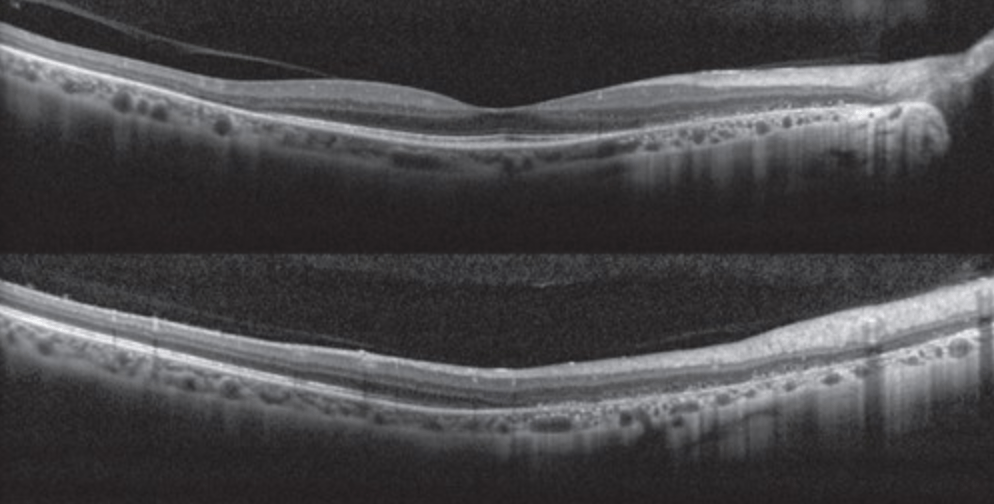

BONUS: 27-year-old woman presents following flu-like illness. Vision is 20/400. Fundus and OCT findings are shown below. Diagnosis? Prognosis?

BONUS: Acute idiopathic maculopathy.

-Vision loss + oftentimes a viral prodrome

-Turbid yellow-gray SRF with pigmentary changes

-OCT with hyperreflective debris in subretinal space +/- SRF.

- Prognosis is good so long as RPE not significantly damaged